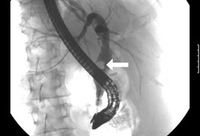

Colangite aguda

A colangiopancreatografia retrógrada endoscópica revela um grande cálculo do ducto colédoco (seta) na parte média deste

Do acervo de Douglas G. Adler; usado com permissão